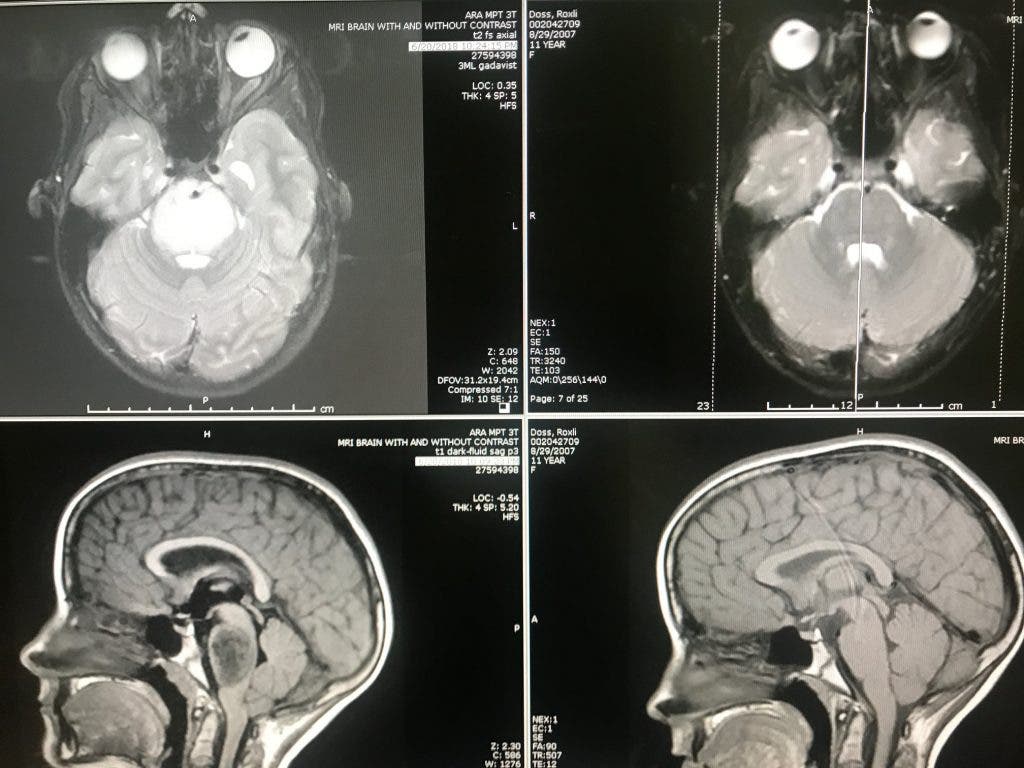

A l’âge de 11 ans, Roxli a suivi plusieurs semaines de radiothérapie, malgré ses faibles chances de survie et l’absence de traitement. Pourtant, après avoir observé les résultats de son IRM (imagerie à résonance magnétique), les médecins ont réalisé que la tumeur avait disparu.

“La première fois que j’ai vu le scan de Roxli, c’était vraiment incroyable”, explique le Dr Harrod. “La tumeur était indétectable, ce qui est hautement inhabituel” a-t-elle ajouté. Un don du ciel pour les parents de la fillette qui attribuent cette “guérison” à une intervention divine.